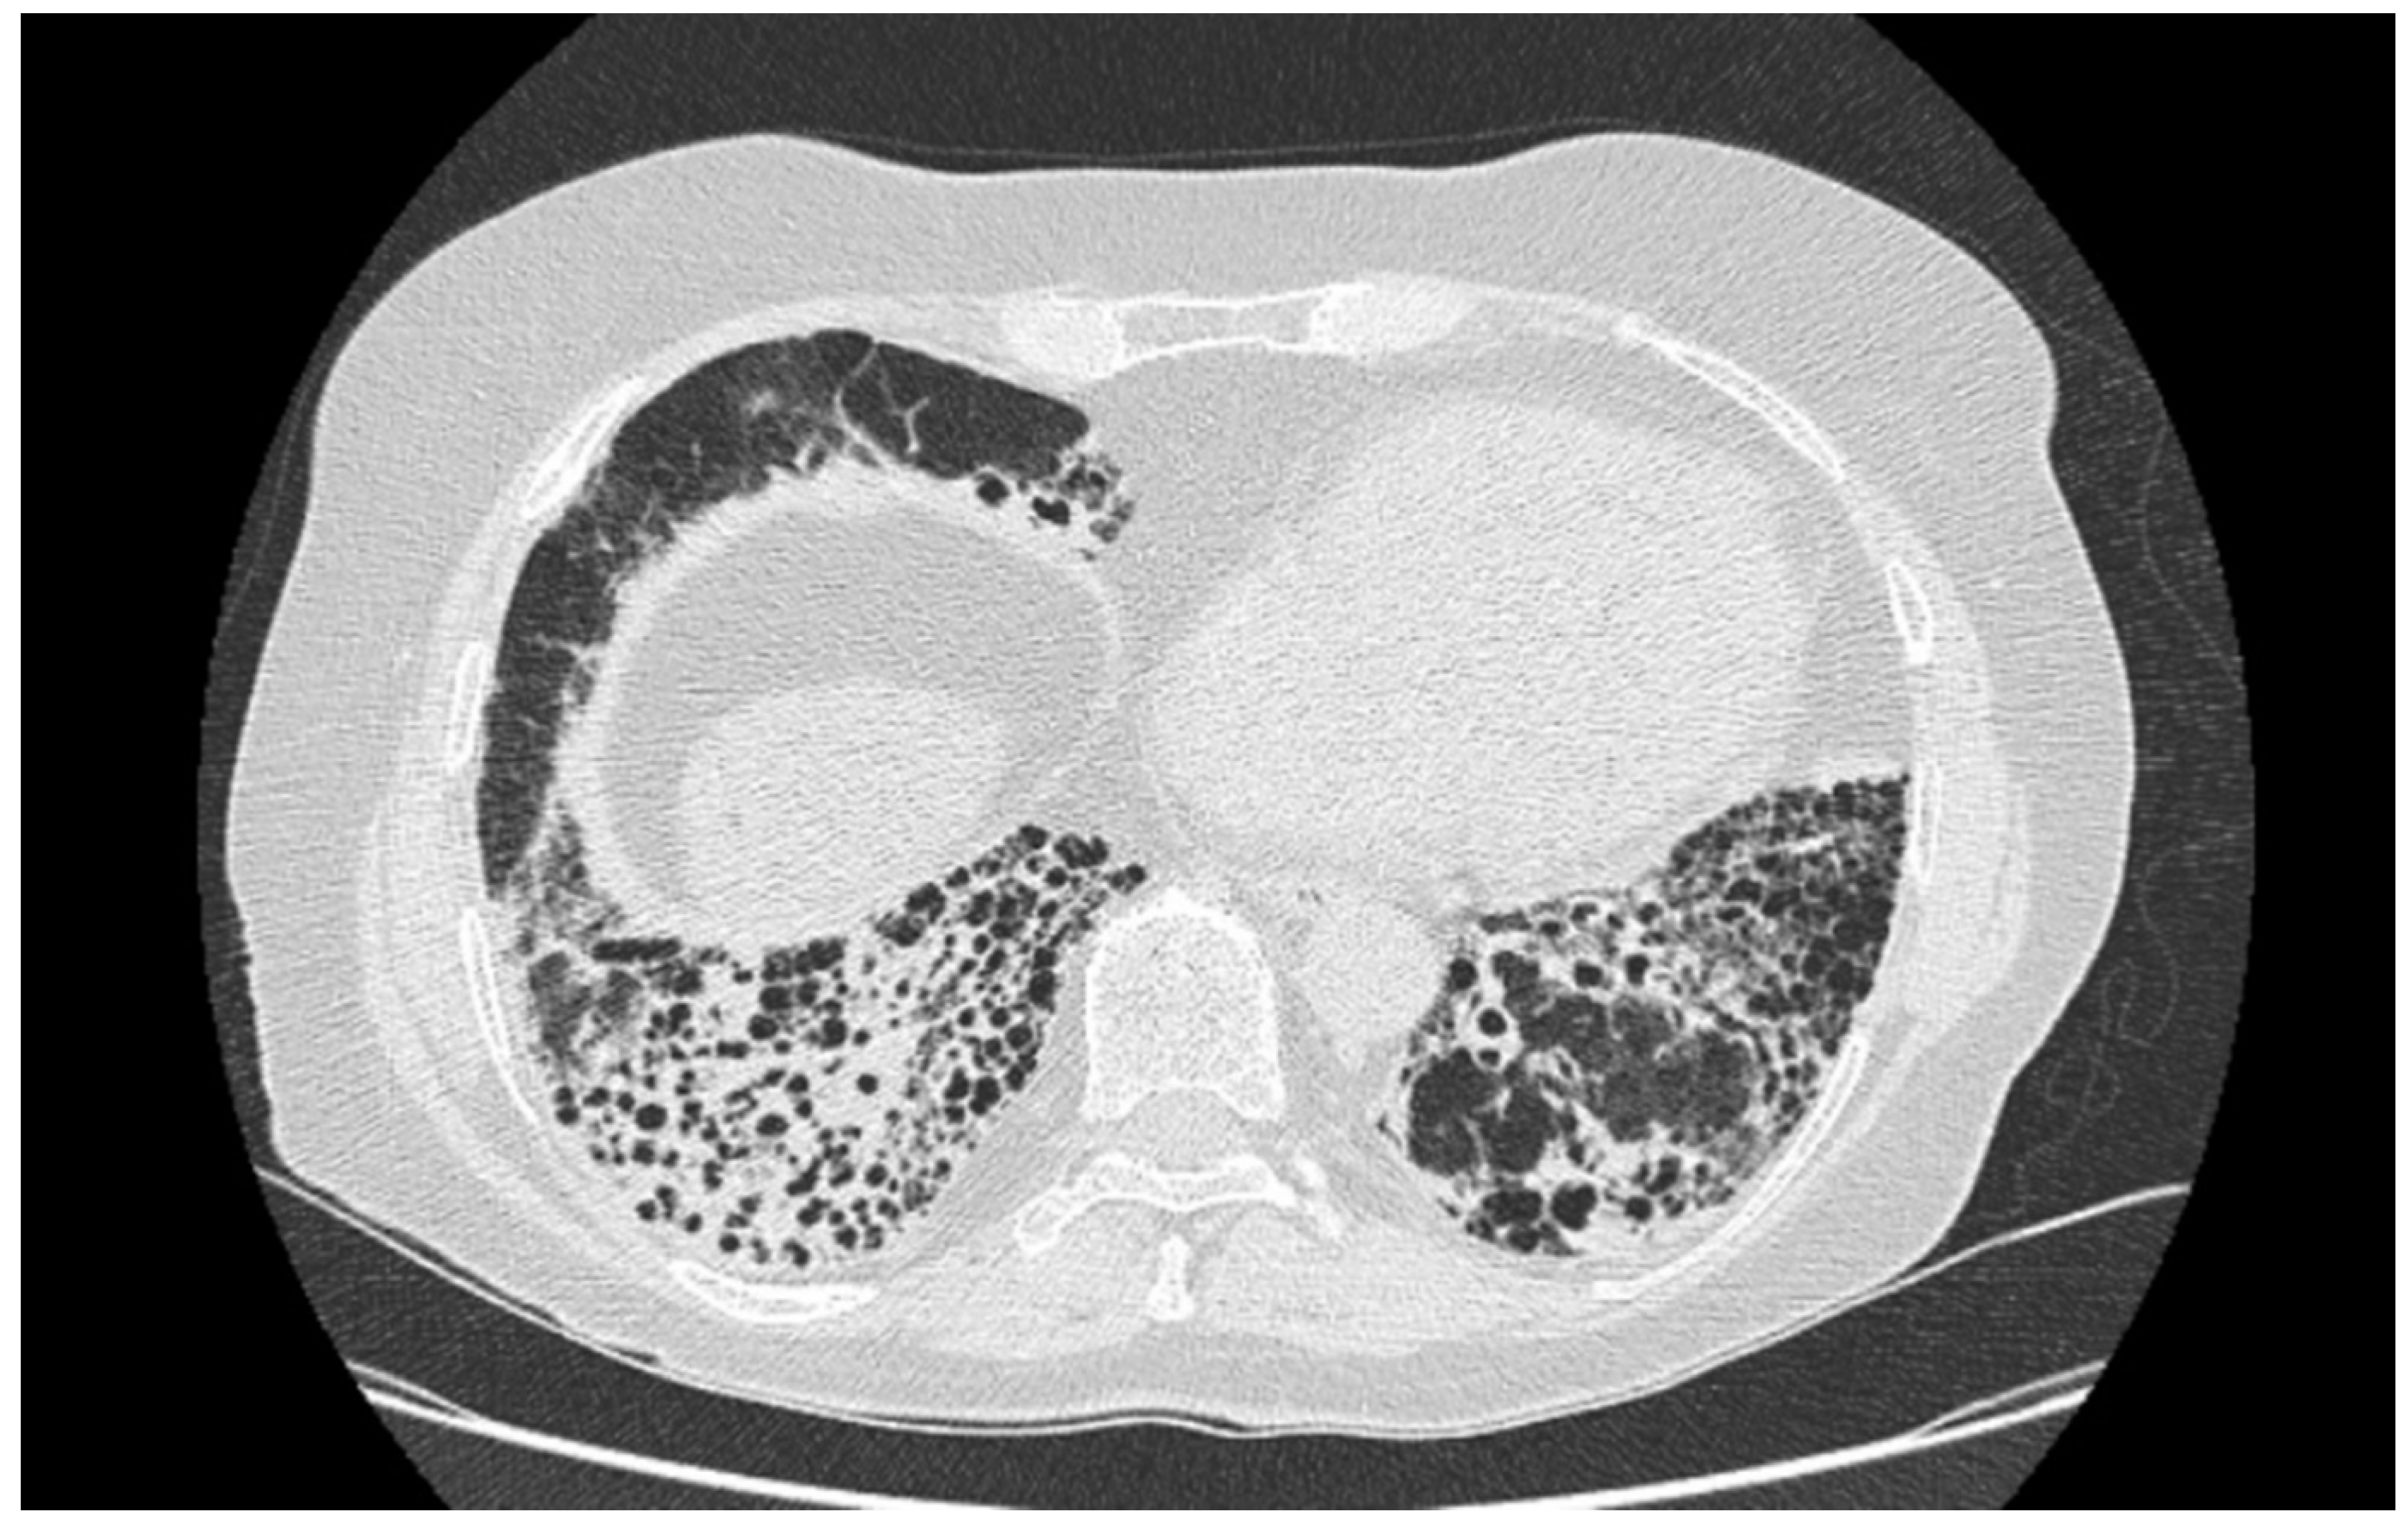

4.1.2. Radiological Testing